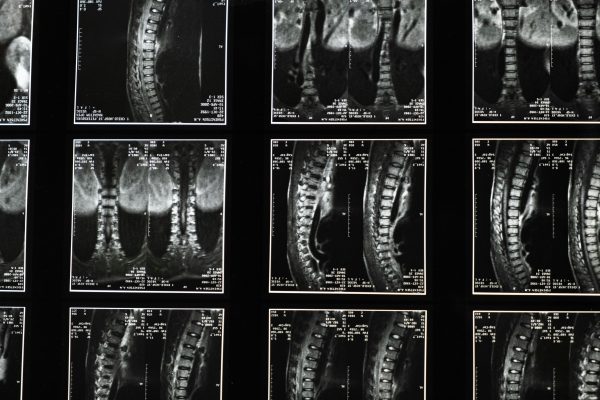

Sciatica pain, a common condition affecting millions globally, arises from irritation or compression of the sciatic nerve—the longest nerve in the bod…